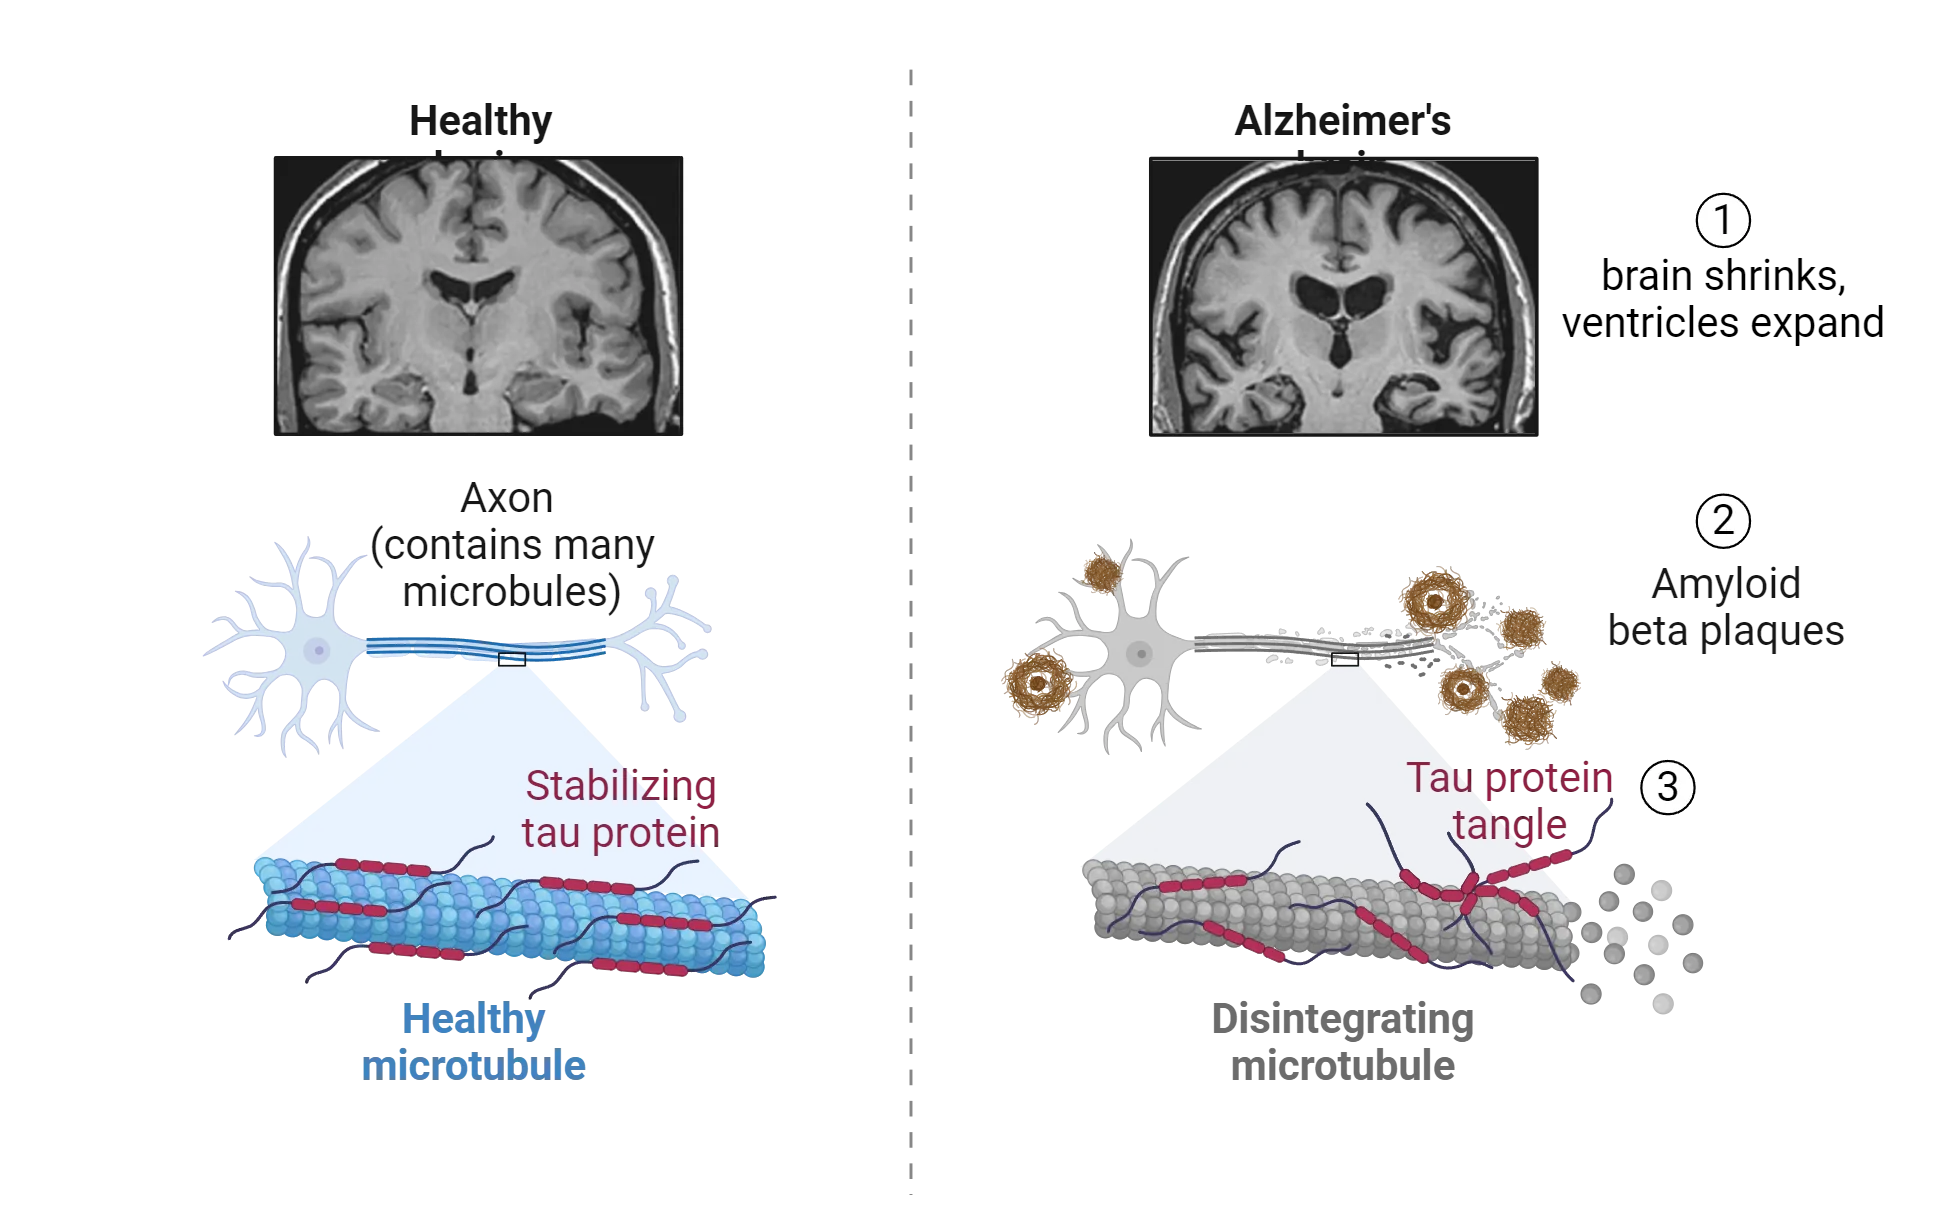

There are three abnormalities that characterize the core pathology underlying Alzheimer’s disease, all shown in Figure 18.7.

Pair of diagrams showing contrast between healthy and Alzheimer’s brains. Alzheimer’s brain: brain shrinks, ventricles expand (shown via MRI), Amyloid beta plaques accumulate outside a diagram of a neuron, tau proteins tangle and microtubules disintegrate inside axons (shown via diagram).

Figure 18.7 Pathology of Alzheimer’s disease

First of all, the brain shrinks in size—ventricles become larger, sulci widen and gyri narrow. This brain atrophy arises due to the progressive widespread death of neurons that is a common feature of all neurodegenerative diseases. Another hallmark pathology of the disease is the accumulation of amyloid plaques, located in the extracellular environment, that appear in high concentrations in the inferior and medial parietal lobe, the medial frontal lobe, the medial temporal lobe, and the posterior cingulate cortex. The plaques are made up of a protein called beta-amyloid, the normal function of which is not well understood. At high concentrations, these proteins can accumulate and bind together and form amyloid fibrils, fibers that bind together and are resistant to degradation. Whether the plaques are a cause of neuronal cell loss or a secondary consequence of another pathological process is still controversial (Herrup 2022). It used to be only possible to confirm the AD diagnosis by measuring amyloid plaque formation post-mortem. However, amyloid protein can now be detected in CSF and using PET imaging. A third biomarker associated with Alzheimer's disease is the accumulation of neurofibrillary tangles, which are abnormalities in the cytoskeleton of neurons. Neurofibrillary tangles are formed by the accumulation of proteins called tubulin associated unit (tau) proteins that build up inside the neurons. Together with amyloid plaques, neurofibrillary tangles have been shown to be negatively correlated with cognitive ability (Braskie et al., 2010).